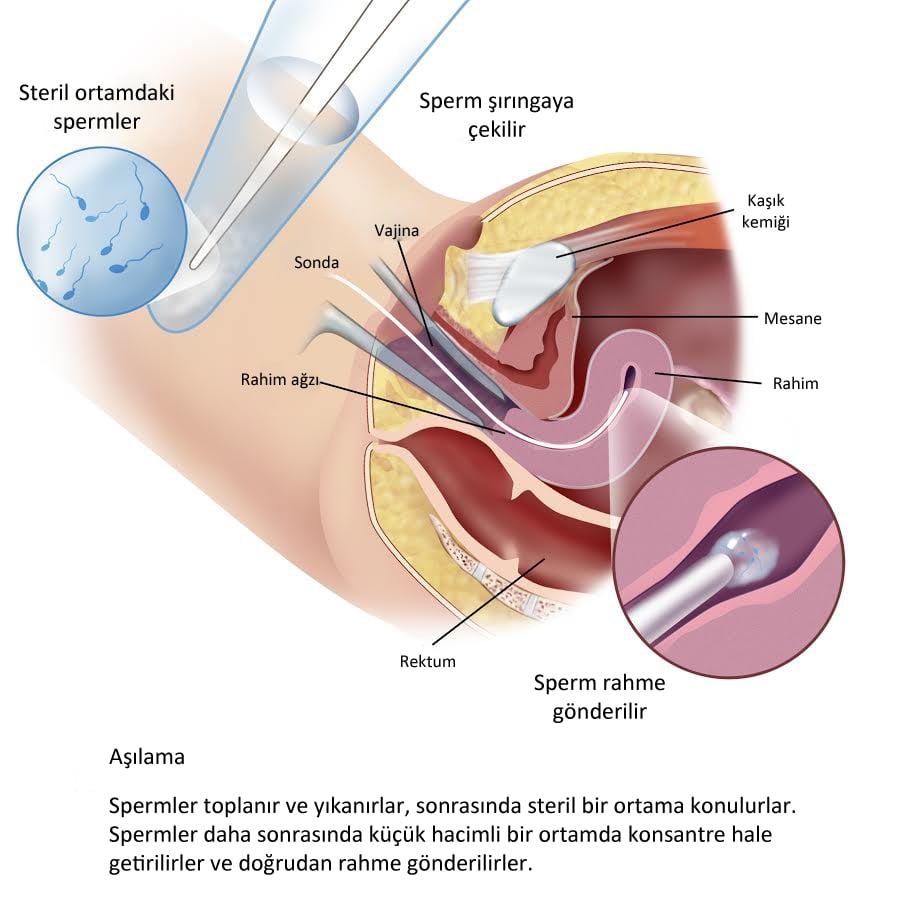

Tüp bebek neden tutmaz. Canım ben de menogon iğne ve klomen kullandım sadece 3 yumurtam oluşmuş çatlatma iğnesi verdi bugün olucam ertesi gün için aşılama dedi ama eşim aşılamayı istemiyor bizde kendimiz deniycez senin nasıl oldu bilgi verir misin. En az 3 tüp bebek tedavi girişiminde iyi kalitedeki embriyo transfer edilmesine karşın hamilelik oluşmaması ya da toplamda 10 ya da daha fazla embriyonun transferine rağmen hamilelik elde edilememesi tekrarlayan tüp bebek başarısızlığı diye adlandırılan bir durumdur. Mrb arkadaşlar menogon kullanan var mı ben ilk defa bu ay başladım daha 1 tane vuruldum bu iğneyle kaçıncı günde büyüdü yumurtalarınız ve bu yolla hamile kalanlar var mı forumlara baktım ama hep eski tarihli bende yeni bir konuda açmak istedim lütfen kullananlar bu forumda buluşalım.

Canımlar adetime az kaldı 3. İğne ile yapılan uyarıda daha fazla yumurta elde edildiğinden ve hapların rahim iç tabakası üzerine potansiyel olumsuz etkilerinden dolayı daha yüksek gebelik. Gonal f ve menogon kullanıp hamile kalanlar var mı. Kadından yumurta toplama ile elde edilen yumurta ve erkekten alınan spermin laboratuvar ortamında birleştirilmesi döllenmesi sonrası elde edilen embriyonun rahim içine nakledilmesidir.